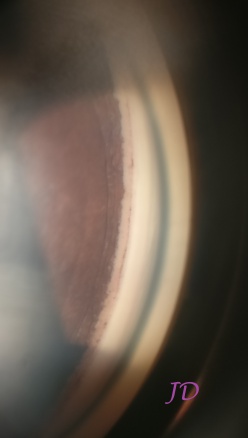

(Video recorded with smartphone showing gonioscopy)